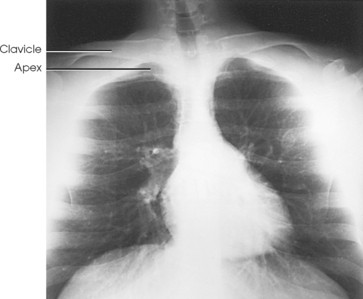

The lungs are the organs of respiration (Fig. 10-4). They are the mechanism for introducing oxygen into the blood and removing carbon dioxide from the blood. The lungs are composed of a light, spongy, highly elastic substance, the parenchyma, and they are covered by a layer of serous membrane. Each lung presents a rounded apex that reaches above the level of the clavicles into the root of the neck and a broad base that, resting on the obliquely placed diaphragm, reaches lower in back and at the sides than in front. The right lung is about 1 inch (2.5 cm) shorter than the left lung because of the large space occupied by the liver, and it is broader than the left lung because of the position of the heart. The lateral surface of each lung conforms with the shape of the chest wall. The inferior surface of the lung is concave, fitting over the diaphragm, and the lateral margins are thin. During respiration, the lungs move inferiorly for inspiration and superiorly for expiration (Fig. 10-5). During inspiration, the lateral margins descend into the deep recesses of the parietal pleura. In radiology, this recess is called the costophrenic angle (see Fig. 10-5, B). The mediastinal surface is concave with a depression, called the hilum, that accommodates the bronchi, pulmonary blood vessels, lymph vessels, and nerves. The inferior mediastinal surface of the left lung contains a concavity called the cardiac notch. This notch conforms to the shape of the heart.

Fig. 10-4 A, Three views of the lung. B, CT axial image through the thorax. Right and left lungs are shown in actual position within thorax and in relation to heart. Note nodule in right anterior lung (arrow). (B, Courtesy Siemens Medical Systems, Iselin, NJ.)